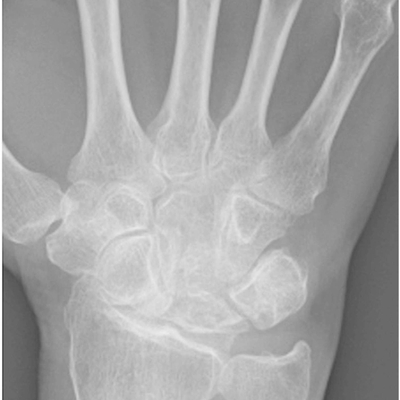

Click on an image below to view more info.